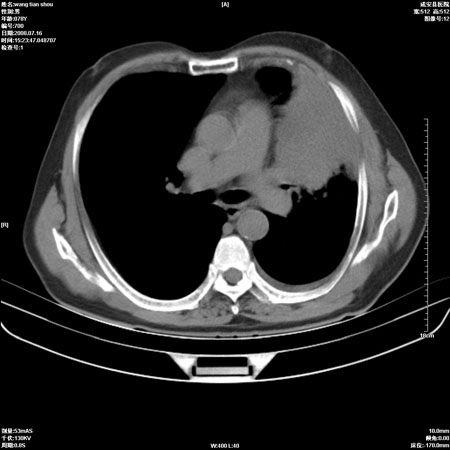

以下是引用qingjing在2008-7-16 19:55:00的发言:[br]1、左上肺不张并堵塞性炎症,建议支气管镜详查;[br]2、左侧胸腔少量积液。

以下是引用wzr在2008-7-16 20:26:00的发言:[br]左肺肺不张伴阻塞性肺炎!另:左侧胸腔少量积液。建议纤支镜检查!